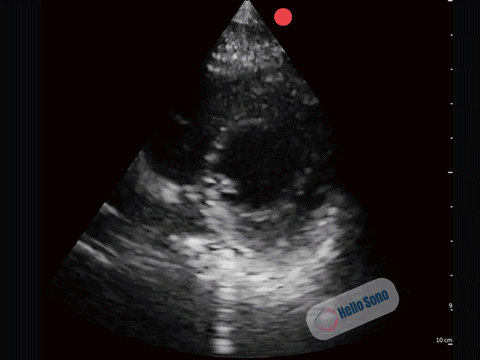

Clip  2: Normal parasternal short-axis view at the level of the papillary muscles.

In a normal PSSA view:

• The left ventricle appears circular

• The interventricular septum maintains its natural curvature

• The right ventricle is clearly smaller than the left ventricle

The left ventricle should resemble a symmetric donut. When it takes on a D-shape, right-sided pressures are elevated.